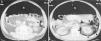

Un varón de 53 años acudió a un hospital comarcal por disnea de reposo, sudoración y dolorimiento en costado y hemiabdomen izquierdo de tres días de duración. Sus antecedentes personales incluían hipertensión arterial tratada con candesartán, tabaquismo y carcinoma epidermoide de lengua tratado con resección quirúrgica y posterior radioterapia y quimioterapia. La exploración puso de manifiesto una hipoventilación en el hemitórax izquierdo y un abdomen distendido, timpanizado, no doloroso y sin signos de irritación peritoneal. La presión arterial fue de 115/85 mmHg, el pulso de 123 latidos/minuto, la temperatura de 37,2 ºC. Los principales datos analíticos fueron: creatinina 3,9 mg/dl, urea 180 mg/dl, glucosa 193 mg/dl, leucocitos 24,4 miles/µl con un 95,7% de neutrófilos, hemoglobina 14,2 g/dl y gasometría arterial basal con pH 7,35, PaO2 64,7 mmHg, PaCO2 27,8 mmHg y bicarbonato 16 mmol/l. La radiografía de tórax mostró un neumotórax izquierdo y neumoperitoneo bilateral. Tras colocar un tubo de tórax anterosuperior, se realizó una tomografía computarizada toracoabdominal que reveló un neumotórax anterior izquierdo residual, aire mediastínico, neumoperitoneo masivo, aire pericólico libre intraperitoneal y retroneumoperitoneo (fig. 1). Seguidamente, se remitió al paciente a nuestro hospital para cirugía y cuidados postoperatorios. La intervención quirúrgica puso de manifiesto una diverticulosis sigmoidea y una perforación diverticular al espacio intraperitoneal y retroperitoneal. Se realizó una resección del sigma y colostomía tipo Hartmann. Inicialmente fue tratado con imipenen y teicoplanina, pero al sexto día de postoperatorio tuvo una sepsis grave por neumonía nosocomial derecha por Klebsiella pneumoniae y Streptococcus milleri que requirió ventilación mecánica y soporte vasoactivo con noradrenalina. El paciente falleció días más tarde a consecuencia de una hipoxia refractaria secundaria a un distrés respiratorio agudo.

Figura 1. Una tomografía computarizada abdominal con contraste evidencia neumoperitoneo masivo (N), aire pericólico izquierdo extraluminal e intraperitoneal (flechas) (A) y retroneumoperitoneo que delimita el riñón izquierdo (flechas) (B).